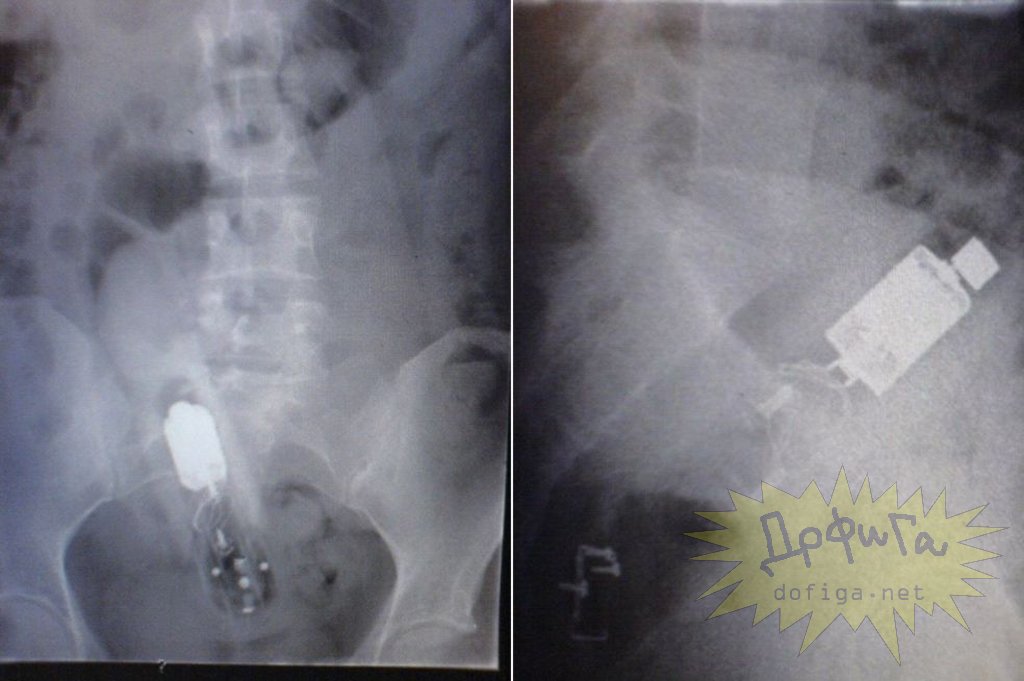

アナルに ”何かしら” を突っ込んで取れなくなってしまう人たちは意外に多いみたいで、そんな人たちのレントゲン写真を集めたギャラリー[13]images